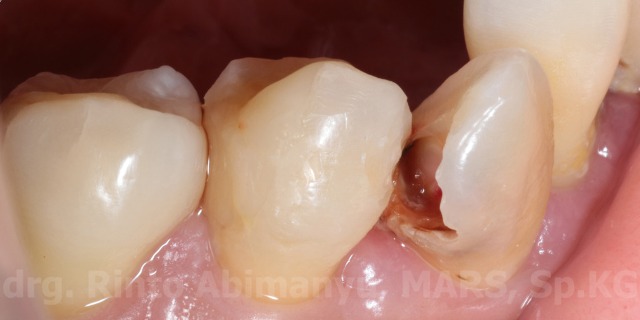

Foto klinis sesaat setelah pengisian….

Setelah dilakukan pengisian

dan ini foto klinis setelah selesai penambalan…

Kondisi akhir setelah selesai perawatan